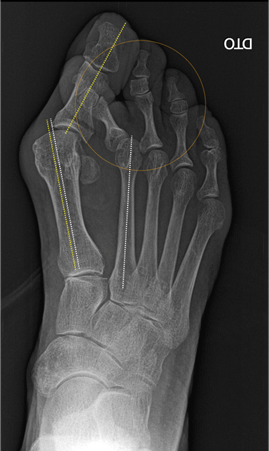

Geralmente o estudo é complementado com exames auxiliares de diagnóstico, como a radiografia dos pés em carga. Neste exame, é realizada a medição de certos ângulos, que irá orientar o tipo de tratamento mais adequado. Em casos selecionados poderá ser necessário a realização de TAC ou ressonância magnética.

Os procedimentos cirúrgicos são adequados à deformidade que o doente apresenta (exame objetivo e radiografias). As mais utilizadas são as osteotomias distal do 1ºmetatarso em chevron e osteotomia de Akin da falange proximal do hallux. Em casos muito severos, em que haja uma grande artrose da articulação metatarsofalângica do hallux, a artrodese (fusão desta articulação) pode estar indicada para controlo sintomático e de realinhamento do pé.